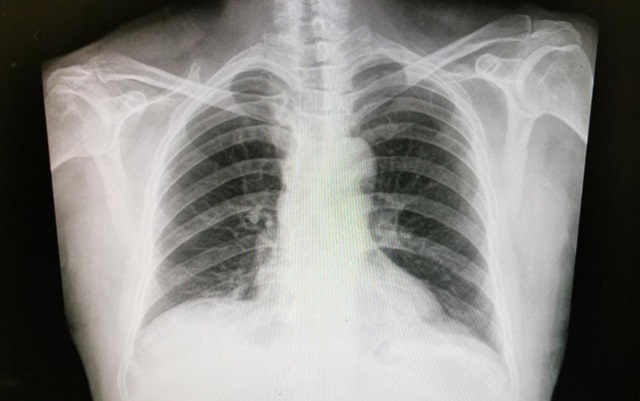

De acuerdo con el especialista, se pueden indicar estudios como radiografía de tórax, tomografías computarizadas e imágenes de resonancia magnética para identificar el interior de los pulmones; sin embargo, para detectar mutaciones genéticas e identificar el tipo de cáncer que se está desarrollando se analizan muestras del tejido pulmonar para evaluar la opción terapéutica más conveniente.